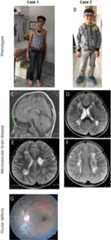

Figure 1. Selection of phenotypes, brain magnetic resonance images, and ocular defects of 2 cases.

(A) Case 1 (homozygous missense [p.Gly1278Ser] inCOL4A1), aged 16 years at the last follow-up, had good academic skills with a marfanoid appearance, mild hemiparesis, partial seizures, and ocular defects. EEG was abnormal. Brain MRI findings showed that diffuse PVL with left ventricular enlargement with small porencephaly and thinning of the body part of the corpus callosum were stable even after 6 years. (B) Case 2 (homozygous missense [p.Gly1278Ser] inCOL4A1), aged 10 years at the last follow-up, had good academic skills with mild hemiparesis and ocular defects. EEG was normal. Brain MRI findings showed that PVL with right mild ventricular enlargement was stable even 6 years later. (C) T1-weighted sagittal image of case 1, showing thinning of the body part of the corpus callosum. (D) T2-weighted axial image of case 2, showing diffuse PVL with right mild ventricular enlargement. (E) T2-weighted axial image of cases 1, showing diffuse PVL with left ventricular enlargement and small porencephalic cyst. (F) T2-weighted axial image of cases 2, showing diffuse bilateral deep white matter leukoencephalopathy. (G) Ophthalmoscopic examination of case 1 showing hypoplastic optic discs and tortuosity of retinal veins. PVL = periventricular leukoencephalopathy.

His initial physical examination revealed a marfanoid appearance with disproportionately long arms and legs compared with the trunk. However, he had no signs of wrist (Walker) or thumb (Steinberg), or joint hypermobility or arachnodactyly, that are typical signs of Marfan syndrome. Cranial nerve examinations and eye movements in all directions were normal. He was using hypermetropic glasses. Ophthalmologic examination revealed bilateral megalocornea, trabeculodysgenesis, nebular corneal opacity, hypoplastic optic discs, and tortuosity of retinal venous vessels, findings that were suggestive of a congenital cataract and glaucoma (figure 1G). Neurologic examination revealed mild unilateral weakness with hemiparetic gait, increased reflexes, and Babinski sign on the right. He was making good academic progress at school and communication with the social environment.

Brain MRI of patient 1 showed diffuse periventricular leukoencephalopathy (PVL) with left ventricular enlargement, small porencephalic cysts, and thinning of the body part of the corpus callosum (figure 1, C and E). Brain MRI analysis was performed twice, at ages 3 and 9 years, and no differences were seen between the 2 MRI analyses. Brain MRI angiography analysis was normal at age 9 years.

Brain MRI showed diffuse PVL with right mild ventricular enlargement (figure 1, D and F). Brain MRI analysis was performed when the patient was aged 3 and 8 years. There were no differences in MRI findings that were performed with 5-year interval. Brain MRI angiography analysis was normal at age 8 years. He was making good academic progress at school and communication with the social environment, like his affected brother.